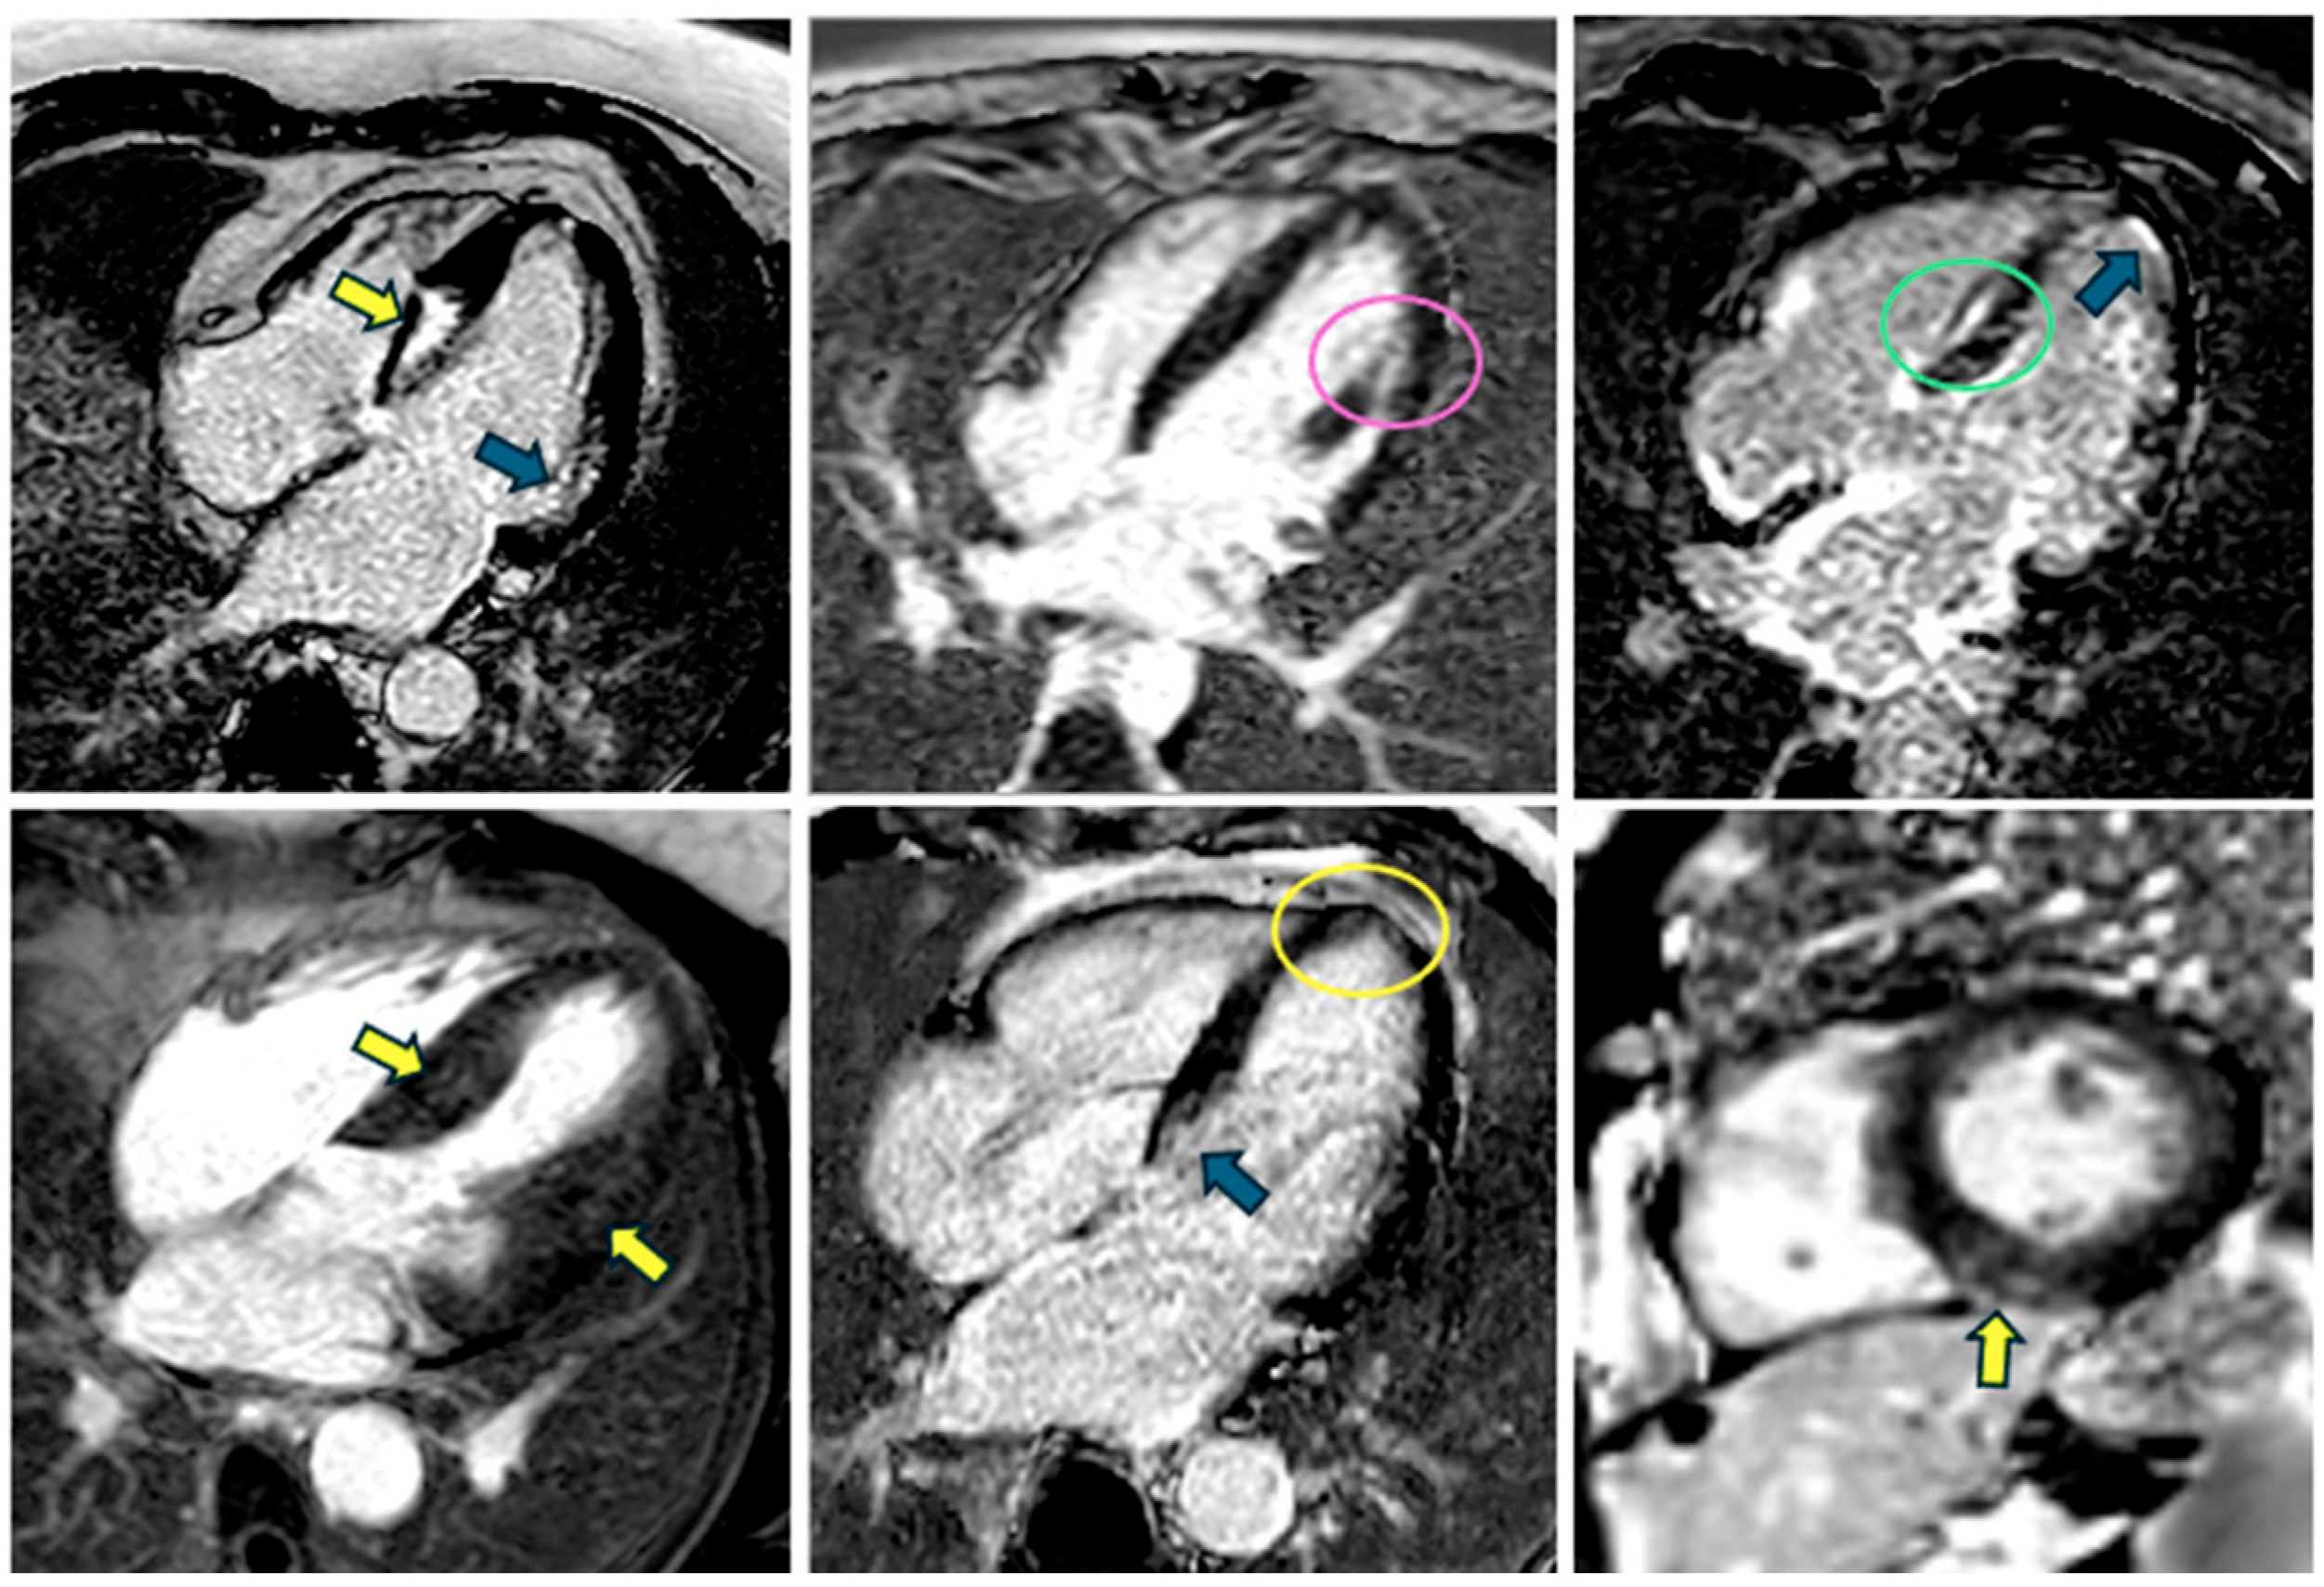

5.2. T1 and T2 Mapping

5.3. Late Gadolinium Enhancement

5.4. Perfusion